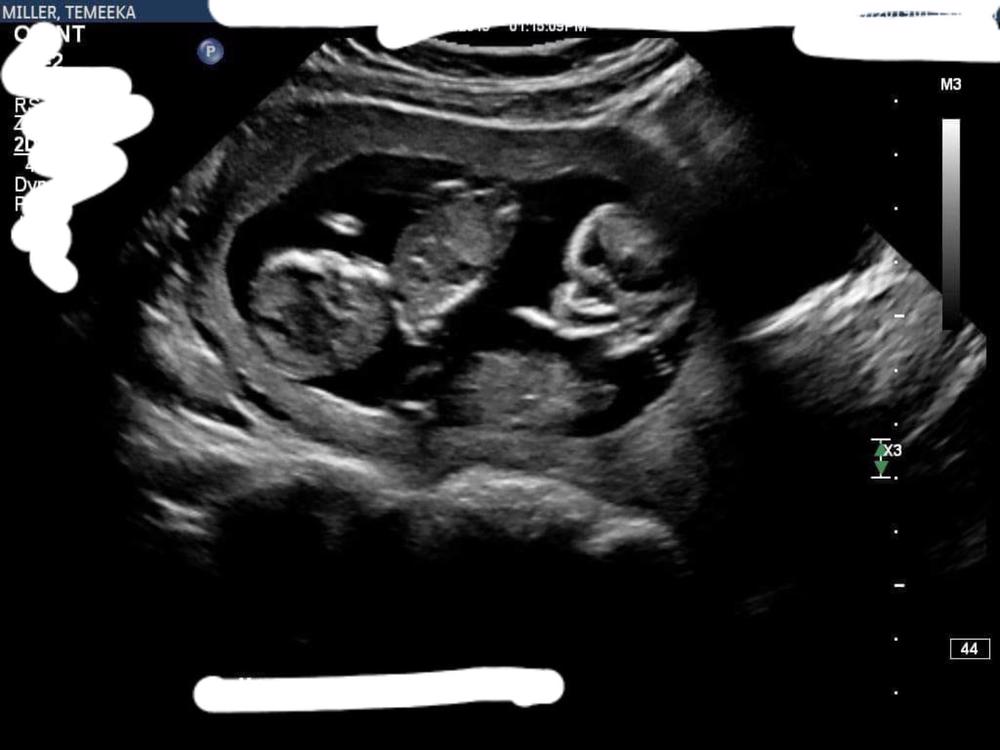

Our beautiful Faith has been diagnosed with Bilateral MCDK along with other health issues, she has a 1% chance of survival

At 20 weeks when we found out our Twin B which we have named Faith has less than a 1% chance of survival it broke us, all our plans stopped, we didn't buy anything, we cancelled our gender reveal our baby shower and completely shut everything out.

Our beautiful Faith lost all her fluid between 16-20weeks, she has been diagnosed with Bilateral multicystic kidneys, her lungs have not developed due to this so she will not be able to breathe when born without assistance but due to the fact of losing fluid so early they cannot intervene and assist her with breathing without damaging her lungs or killing her on the machine, her heart is enlarged on the left side which also has fluid around it.

A human can simply not survive without at least 1 kidney functioning. The doctors expect her to live for the duration of our pregnancy but pass away within minutes of being born. We are holding onto so much hope that a small part of one of her kidneys start working and that she beats the doctor’s odds and be the first case they have seen in over 20 years survive. But as time gets closer with no change our hope doesn’t fade but our reality slowly becomes a lot harder.